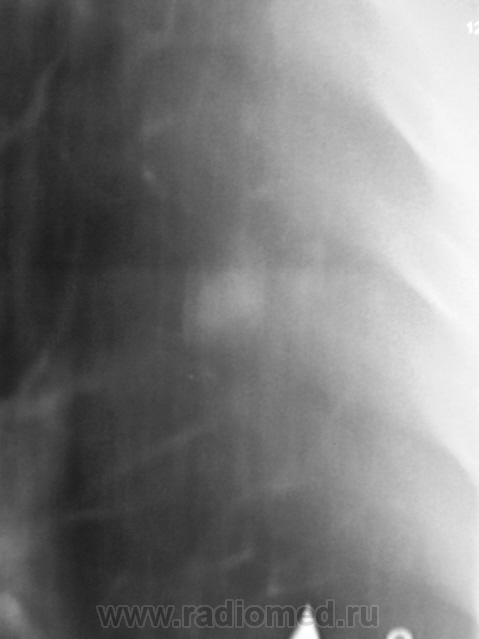

ТОМОГРАФИЯ.

Второй срез.